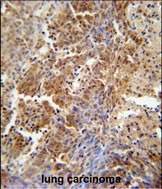

分类: 科研抗体货号: P30881别名: UPF0577 protein KIAA1324-like, Estrogen-induced gene 121-like protein, hEIG121L, KIAA1324L, EIG121L应用: WB,IHC,FCM反应种属: Human, Mouse